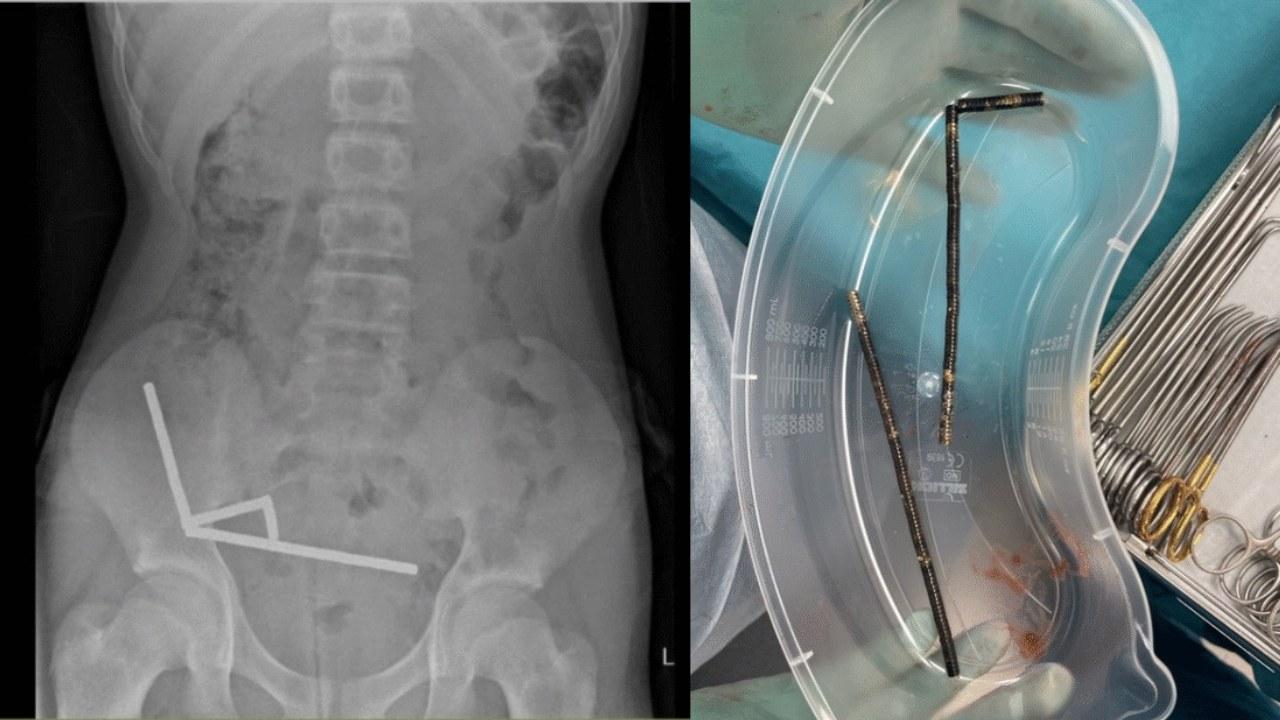

X光中顯示,這些小磁鐵在他腸子裡的不同部位中形成4條鏈子互相拉扯,並切斷了附近組織的血流,壓力更導致多處壞死。

醫生為他移除磁鐵和部分受損腸道,男童最終在醫院裡住了8天。